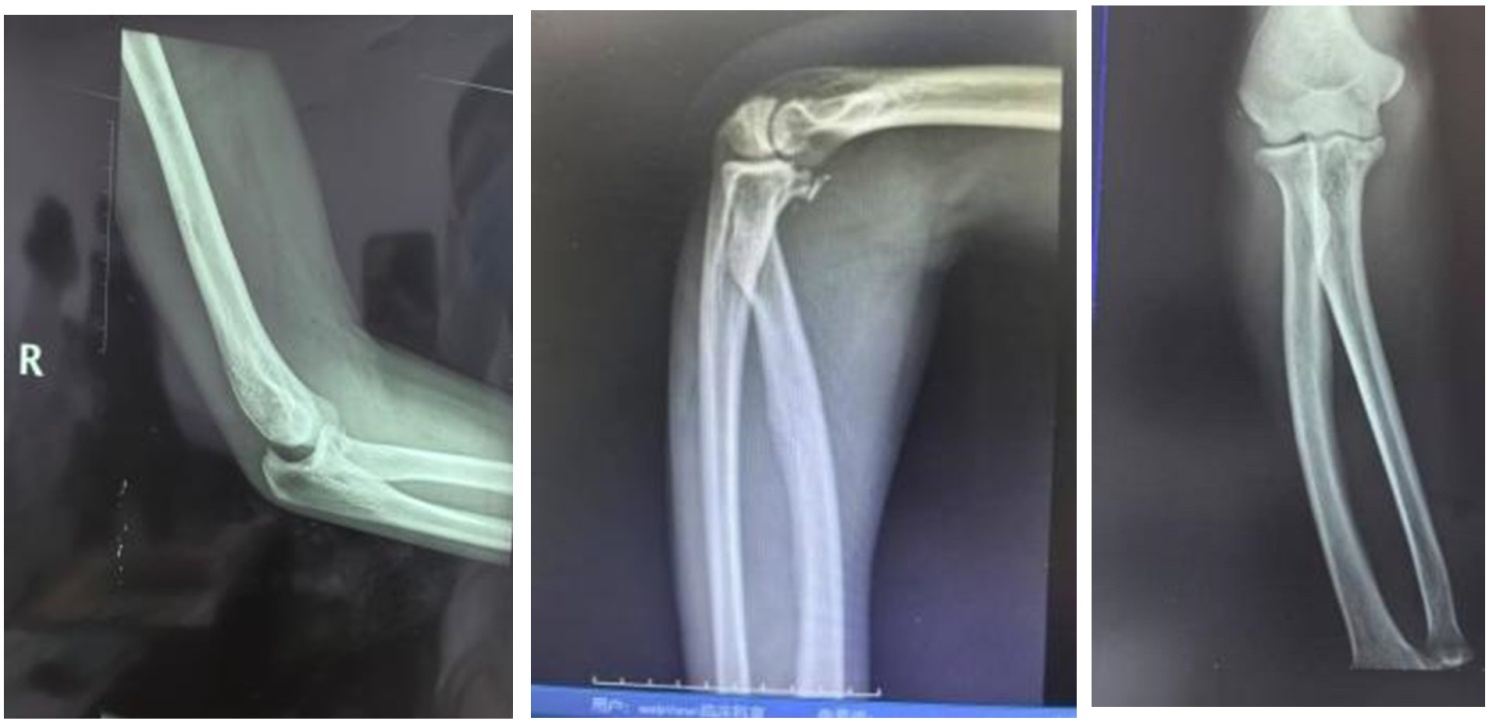

Figure 3. Follow-up X-ray image one and a half months after ulnar coronoid fracture reduction

3. 骨折1月半后复查影像

Figure 4. Clinical appearance of the patient during follow-up visit on December 17th

4. 12月17日复诊患者外观影像

治疗结果:6周后(见图3)患者复查X线影像显示骨折对位愈合良好,前臂旋转及曲肘功能可,5月(见图4)后复诊患者功能恢复正常。